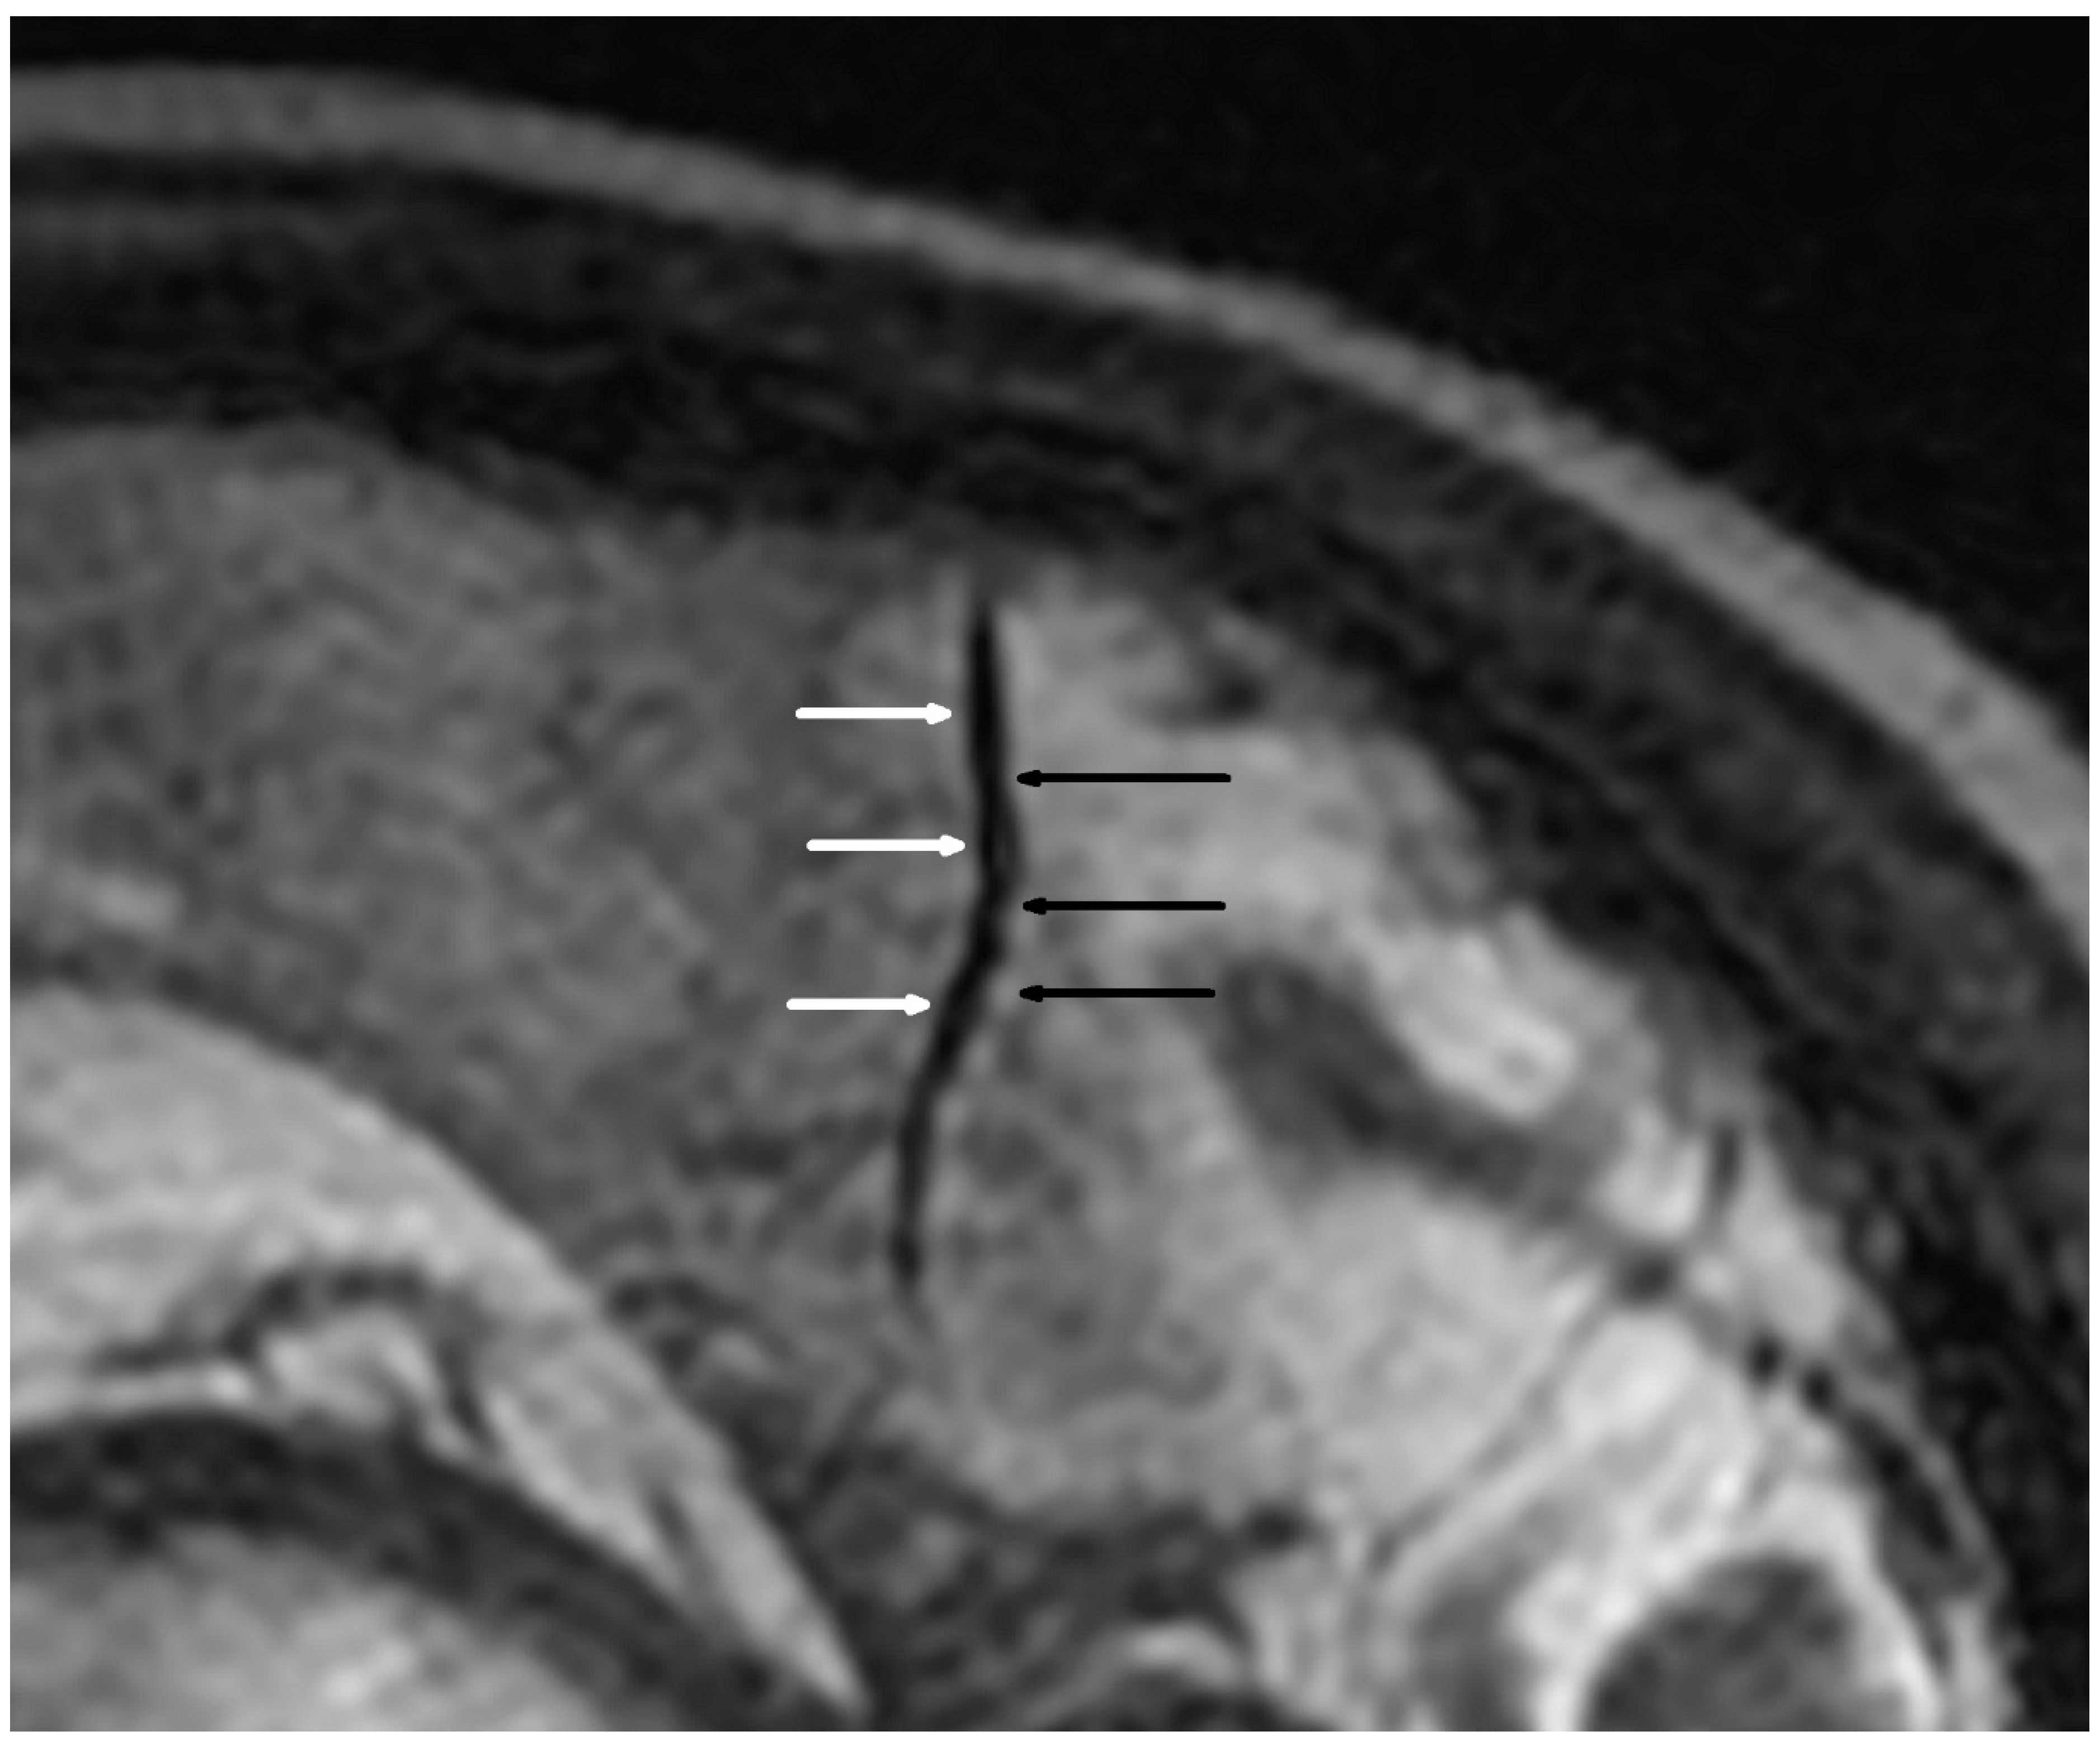

Figure 1.

Alternating narrowing and dilatation in the intracranial vessel (sagittal plane). 3D Cube T2 Iso FSE sagittal sequence; black arrow—narrowing; white arrow—widening.

Cerebral MRI in TOF scanning revealed five microaneurysms (dimensions from 1.7 × 1.8 mm to 3.5 × 4.0 mm), and two of them were localized in the right internal carotid arteria. We found only two segmental arterial narrowing in the investigated group. The occurrence of VAND was detected in 16/38 (42.1%) patients (Table 4, Figure 1 and Figure 2). Considering the different quantities of VAND, the BB MRI technique was more diagnostic than the TOF sequence (p < 0.001).